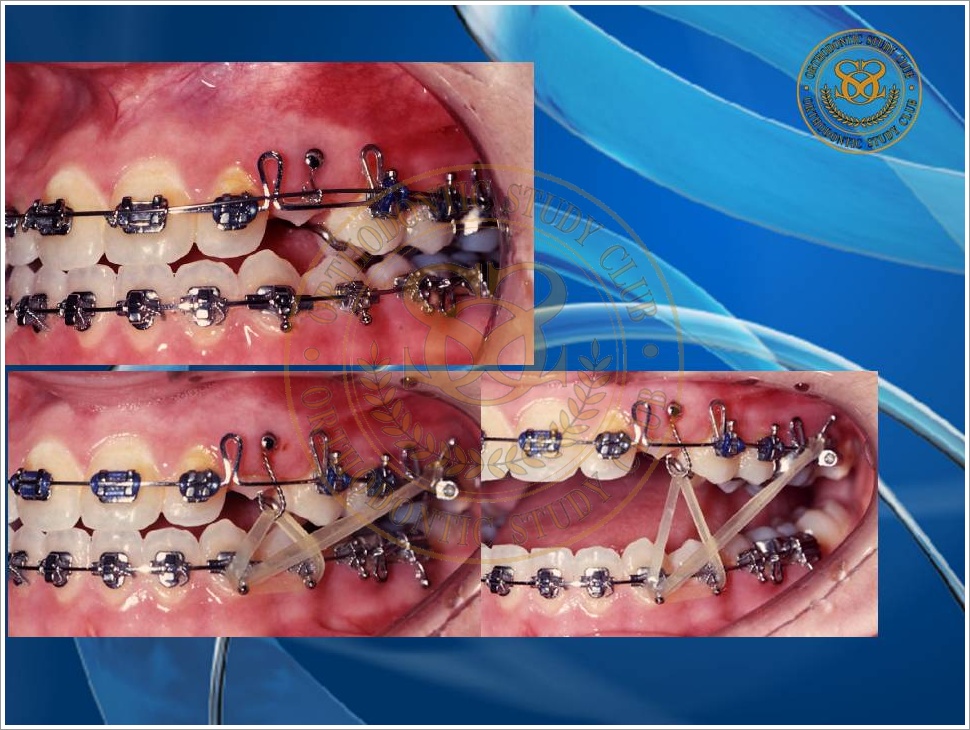

Treatment of Pseudo Class III (Class I Molar Relationship) and management of the embedded maxillary canine (Pt. Miss J.I.)